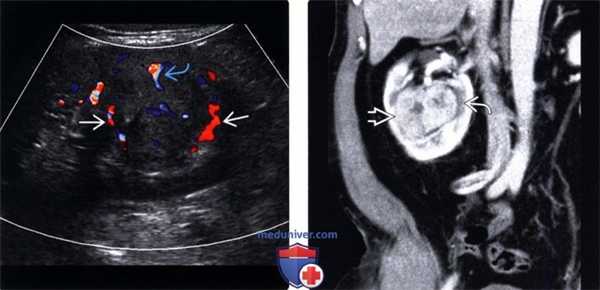

(Слева) МРТ, Т2-ВИ, аксиальная проекция, режим подавления сигнала от жировой ткани: солидное объемное образование, локализованное в латеральном корковом веществе правой почки, которое имеет промежуточную или слегка увеличенную интенсивность сигнала относительно нормальной прилежащей почечной паренхимой.

(Справа) МРТ, постконтрастное Т1-ВИ, коронарная проекция, режим подавления сигнала от жировой ткани: у этой же пациентки обнаружено гиперваскулярнре объемное образование с центральным некрозом в правой почке. Выявлен метастатический рак молочной железы. Ниже метастазов расположены случайно выявленные кисты.

(Слева) Цветовое допплеровское картирование, сагиттальная плоскость: крупное гетерогенное объемное образование, замещающее верхний полюс правой почки (следствие метастатического немелкоклеточного рака легкого). Обратите внимание на внутренний цветовой поток в метастазах. Имеется аналогичного вида объемное образование в контрлатеральной почке (не показано).

(Справа) Последующая контрастная КТ, аксиальная проекция: у этого же пациента выявлены двусторонние гетерогенно окрашиваемые объемные образования почек с областями некроза (следствие метастатического немелкоклеточного рака легких).